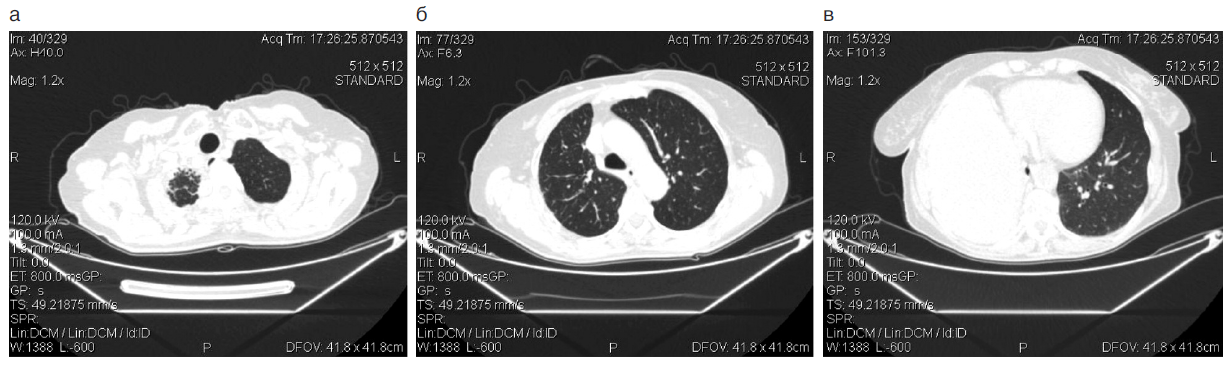

Через 6 нед от начала терапии при КТ (рис. 2) отмечен частичный ответ опухоли – уменьшение на 57% суммы размеров контрольных очагов, исчезновение плеврита.

Положительная рентгенологическая динамика сопровождалась уменьшением слабости, кашля, одышки. Пациентка вышла на работу, статус ECOG – 1.

Рис. 2. КТ больной З., 73 года, декабрь 2015 г.

Fig. 2. Computed tomography of patient Z., 73 years old, December 2015.

На протяжении 4 лет больная продолжает получать терапию препаратом осимертиниб. Отмечается минимум побочных действий терапии – сухость кожи, периодически регистрировалась нейтропения 1–2-й степени.

По данным КТ сохраняется частичный ответ (рис. 3).

Рис. 3. КТ больной З., 77 лет, январь 2020 г.

Fig. 3. Computed tomography of patient Z., 77 years old, January 2020.

Длительность ответа к настоящему моменту составила 52 мес (4 года и 4 мес).